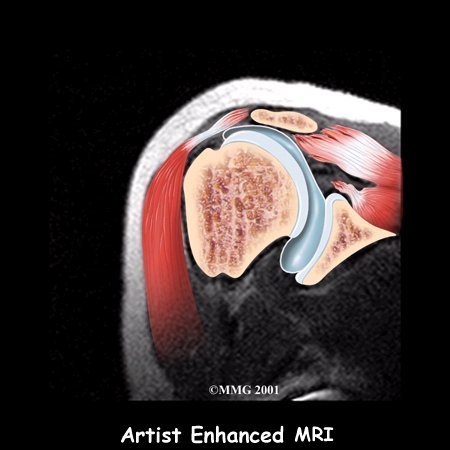

Your doctor may ask you to have a magnetic resonance imaging (MRI) scan.

An MRI scan is a special imaging test that uses magnetic waves to create pictures of the shoulder in slices. The MRI scan shows tendons as well as bones. This test is painless and requires no needles or injections.

Today, the MRI scan is the most common test used to evaluate the shoulder and determine whether surgery is necessary. Your surgeon will be looking for details of your rotator cuff tear and checking for other problems. As mentioned earlier, a tear usually doesn't occur unless the rotator cuff is already weakened by some other problem. Other potential problems include: